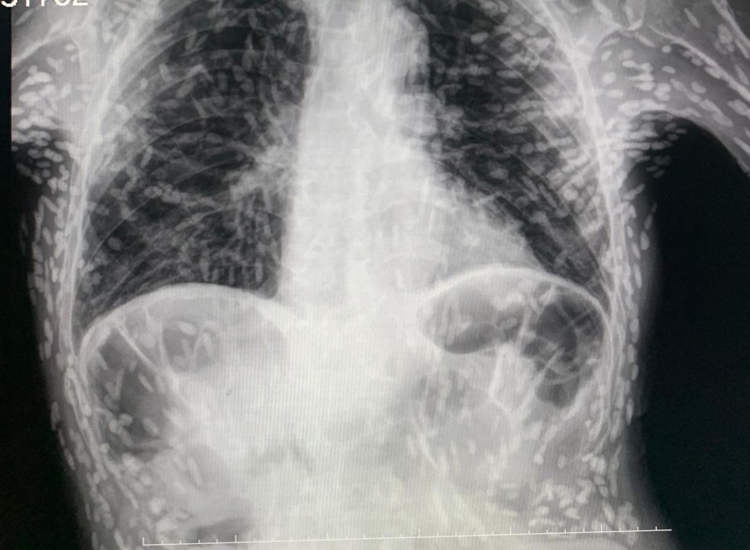

เมื่อเดือนที่ผ่านมา ดร.วิตอร์ โบริน เดอ ซูซา แพทย์ประจำบ้านของโรงพยาบาลเมืองโบตูคาตู ในรัฐเซาเปาโล ประเทศบราซิล ได้เผยแพร่ภาพถ่ายเอกซเรย์ของคนไข้ชายรายดังกล่าว โดยแสดงให้เห็นว่า มีจุดสีขาวกระจายอยู่ทั่วทั้งลำตัว และแขน โดยจุดขาว ๆ เหล่านี้คือ ไข่ของพยาธิตัวตืดที่อยู่ในสภาวะกลายเป็นหินปูน หรือแคลเซียมเกาะ (Calcification) จากการสะสมของแคลเซียมอย่างผิดปกติในเนื้อเยื่ออ่อน ทำให้แข็งกลายเป็นหินปูน

ภาพจาก Twitter Doctor Vitor Borin de Souza